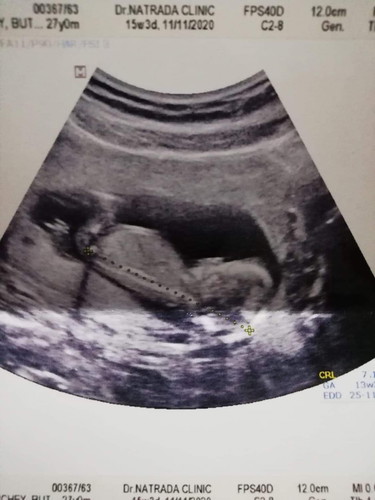

13w 3d

ตอนฝากท้องครั้งแรก นับได้ 15 w กว่าๆ เราเลยไปอัลตราซาวดูน้อง หมอบอก13w ดีใจจัง เบบี้น้อย รักแรกพบ